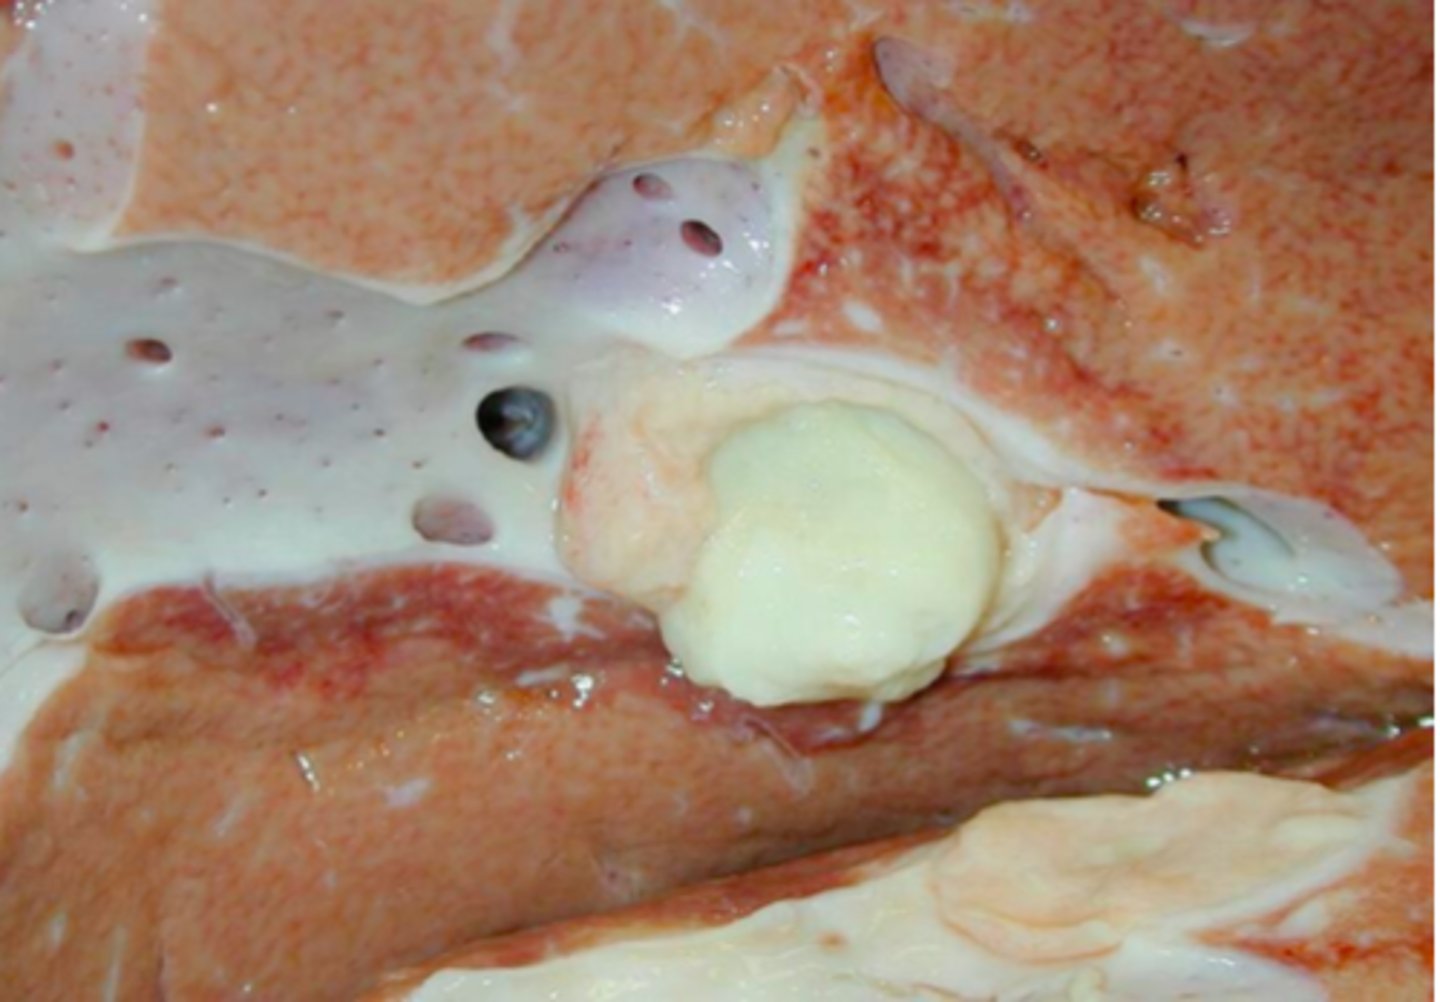

Lever fra okse, hvad er den patoanatomiske diagnose?

diffus ophobning af synligt fedt i form af triglycerider i hepatocytterne

Hvad ophobes i leveren ved Steatosis hepatis?

Lever fra okse, hvad er den patoanatomiske diagnose?

Lever fra okse, hvad er den patoanatomiske diagnose?